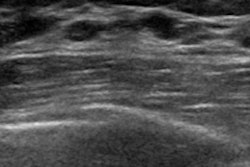

To elucidate these associations, the researchers analyzed data in a previously established cohort of more than 10,000 women who were free from cancer when they enrolled. They identified 289 women who had developed cancer and compared them to 658 similar women who did not. Each woman had received regular mammograms. The researchers included 8,710 single-breast images, representing an average of four time points over a 10-year period for each patient.

Since breast cancer rarely develops in both breasts at the same time, the group analyzed the images of each breast separately. While women's breasts normally become less dense as they age, the researchers found that density declined significantly more slowly in the breasts that later developed cancer than in those that did not.